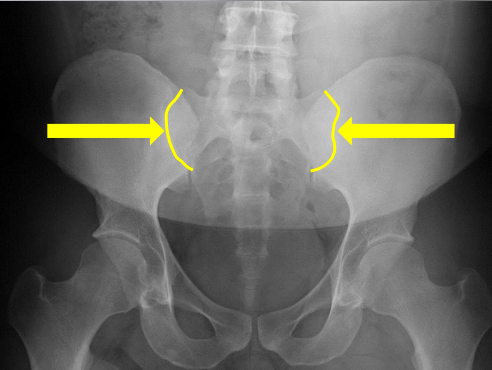

Lateral iliac crests

Medial aspect of ilium